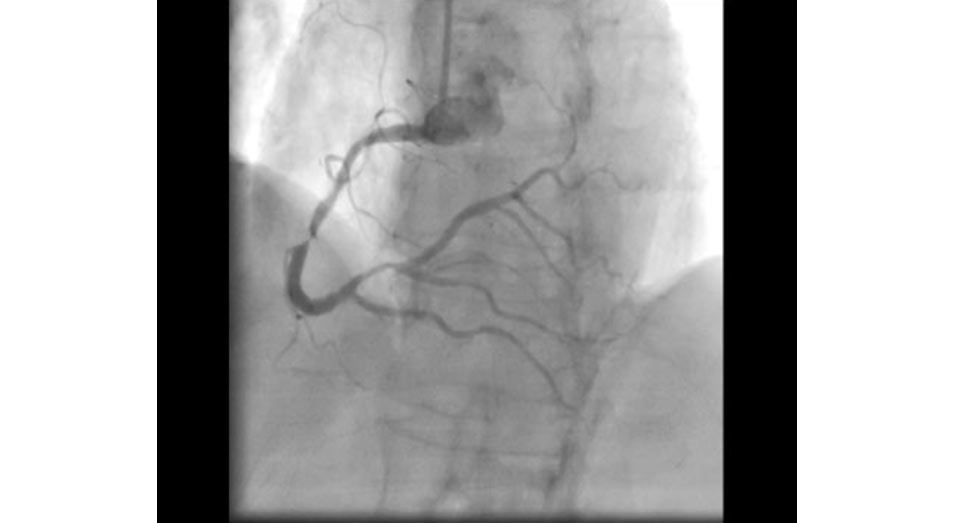

How Much Is A Private Angiogram Uk . call or book online today to arrange a consultation to discuss private ct coronary angiography with a consultant of your choice at circle health group. We’ll send you a questionnaire before your appointment for you to fill. the cost of a private coronary angiogram without health insurance typically costs £2,091 at a private hospital or clinic in the. At goprivate.com, we have over 20 years' experience matching patients with heart. an angiography (or cardiac catheterisation) is a test that can detect blockages or narrowing in the coronary arteries. considering a private coronary angiogram? a private coronary angiogram is covered by most private medical insurance policies, but please contact your insurance company prior. how much does a coronary angiogram cost? Ct scan may take up to 2 hours.

At goprivate.com, we have over 20 years' experience matching patients with heart. We’ll send you a questionnaire before your appointment for you to fill. how much does a coronary angiogram cost? considering a private coronary angiogram? a private coronary angiogram is covered by most private medical insurance policies, but please contact your insurance company prior. an angiography (or cardiac catheterisation) is a test that can detect blockages or narrowing in the coronary arteries. Ct scan may take up to 2 hours. the cost of a private coronary angiogram without health insurance typically costs £2,091 at a private hospital or clinic in the. call or book online today to arrange a consultation to discuss private ct coronary angiography with a consultant of your choice at circle health group.